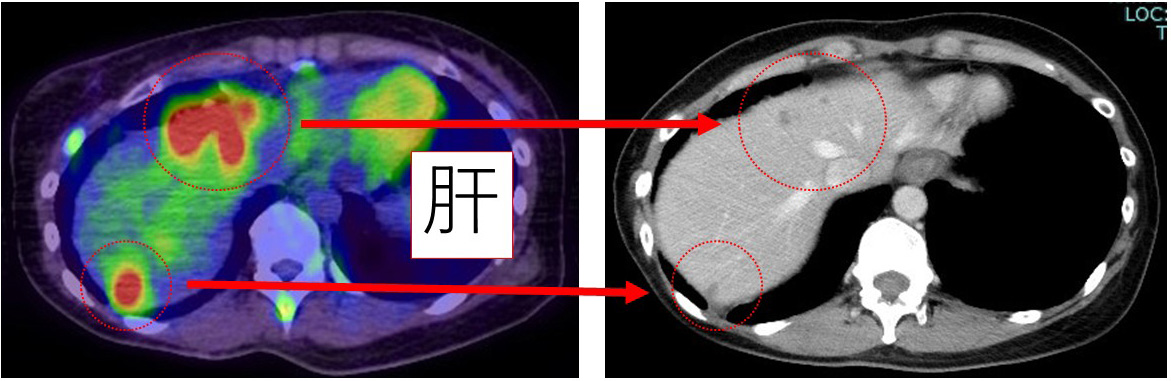

論より証拠! この画像を見てください。

前医でのPET(左)とanthracycline(EC)終了時の当院CT(右)と比べてください。

PETとCTでの比較とはいえ、これだけの効果があるのです。

リンパ節もこの通り。 無論エコーでは全く不明となりました。